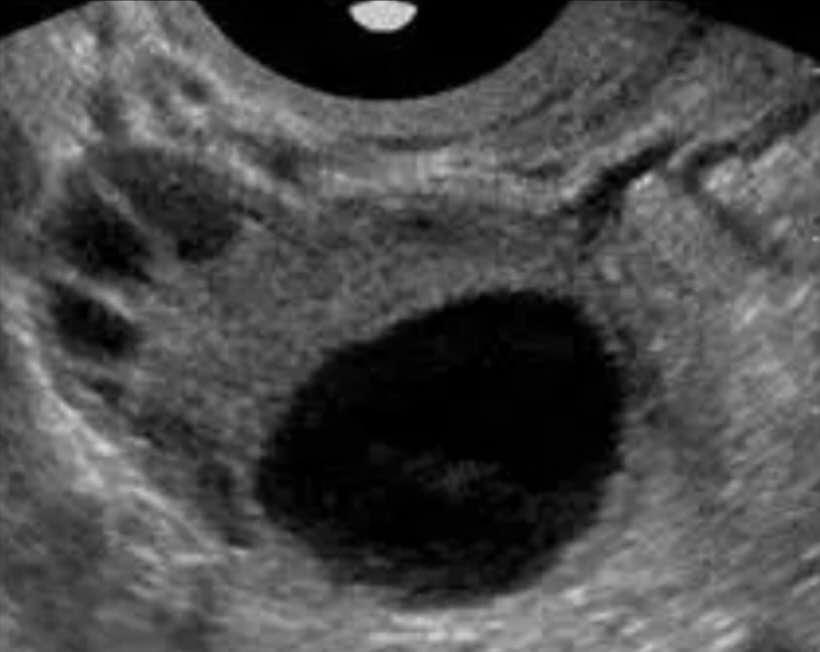

超声下的优势卵泡(虽然黑但是漂亮)

卵泡>18mm时: 为成熟卵泡,此时可诱导排卵